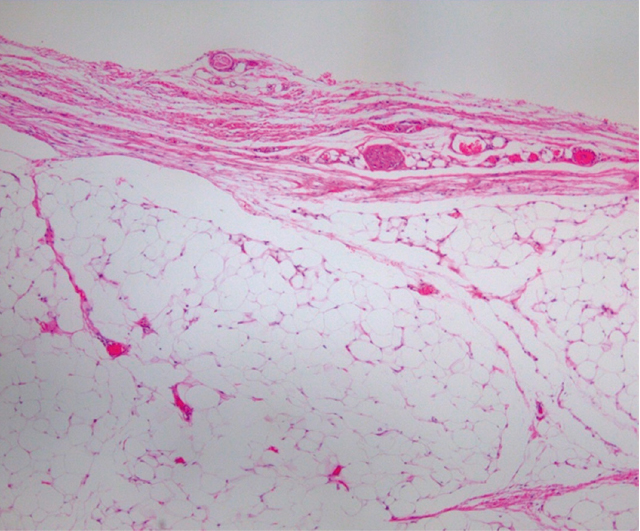

病理組織学的所見:摘出標本は45×13×15mmで,上皮下に成熟脂肪細胞の増殖を認めた.脂肪肉腫を示唆する所見は認めず,病理組織学的に脂肪腫と診断した(Figure 9).

病理組織学所見.上皮下に成熟脂肪細胞の増殖を認める.